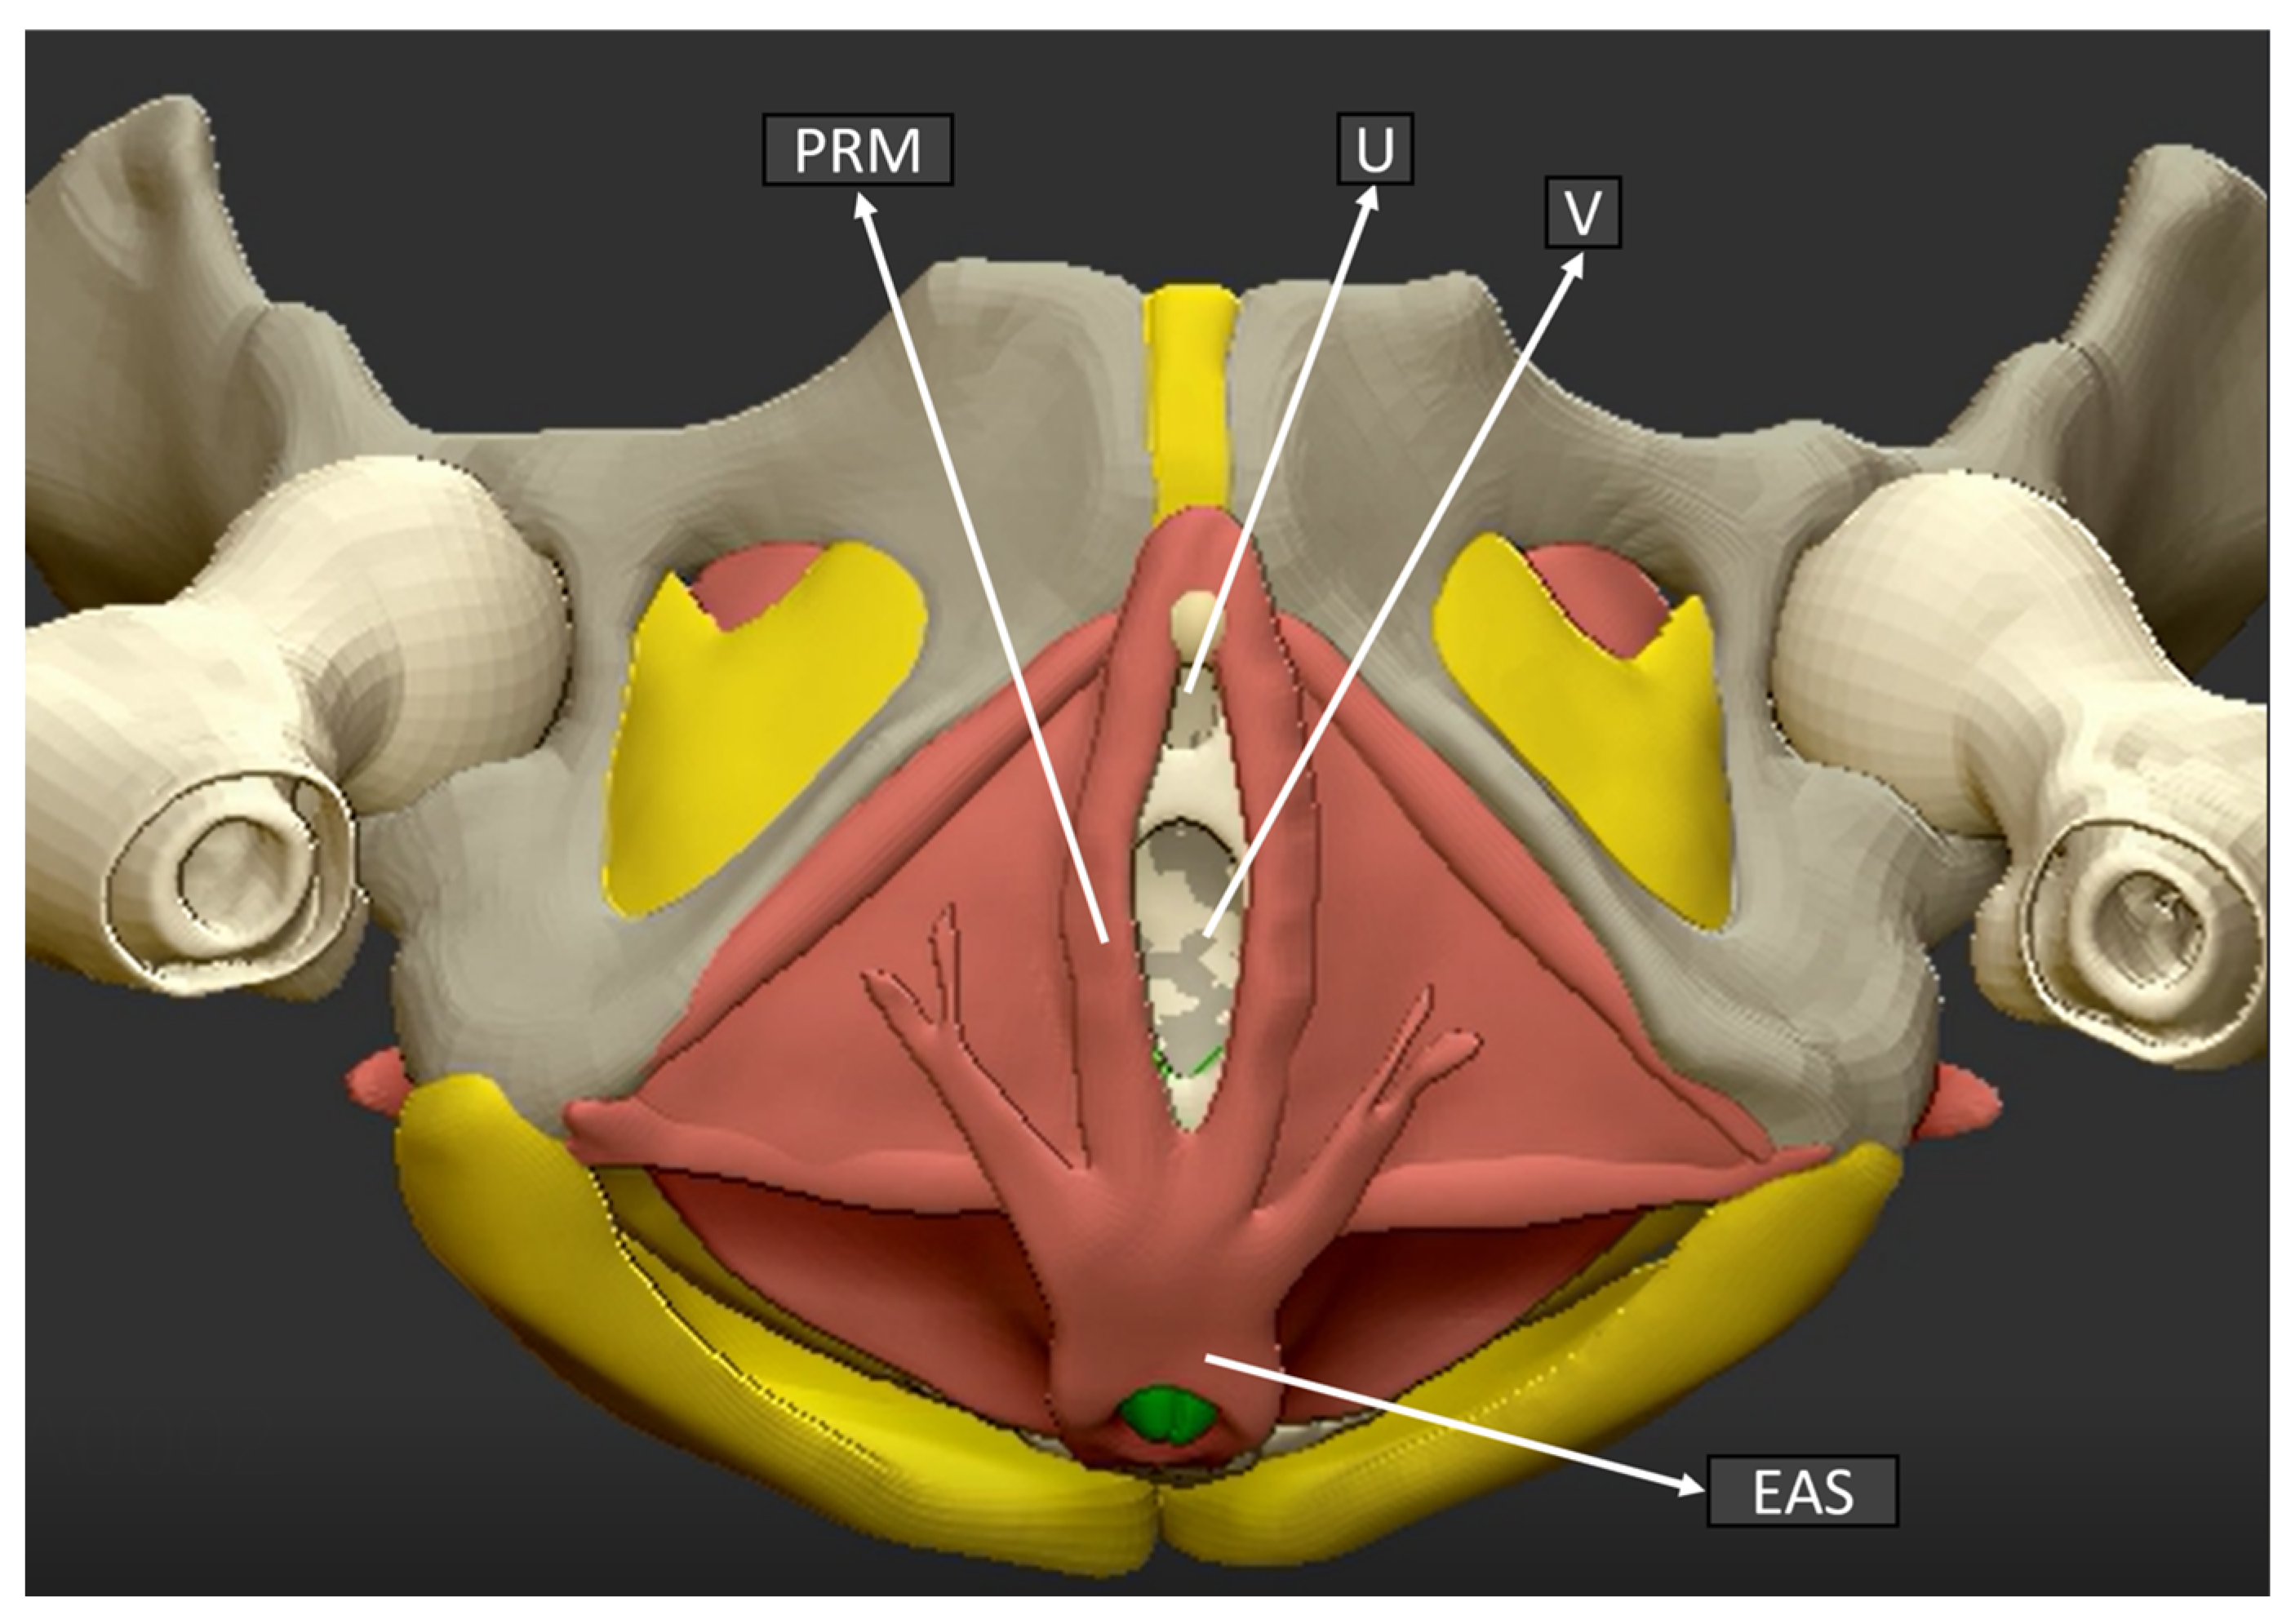

In Figure 3, an anatomical sketch of the coronal plane of the pelvic floor is shown in order to illustrate the exact plane and structures obtained by the 3D ultrasound examination.

Figure 3.

Pelvic floor anatomical structure coronal plane. (U) Urethra, (V) Vagina, (PRM) Puborectalis muscle, (EAS) External anal sphincter.